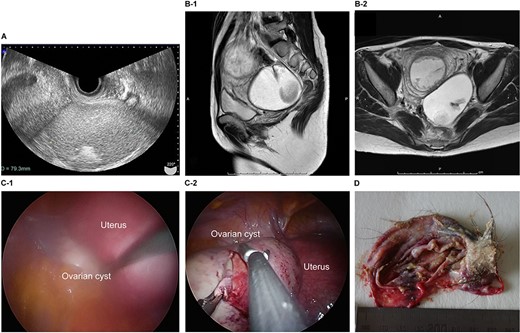

The patient was a 38-year-old, gravida 3, para 1 woman with no familial or medical history. She conceived naturally and was diagnosed at 7 weeks of gestation in another medical facility. She was subsequently referred to our hospital for further examination and operation. Transvaginal ultrasonography (TVUS) revealed a fetus in the uterus and a mass 7 cm in diameter on the right ovary. Magnetic resonance imaging (MRI) revealed right ovarian cystic tumors with fat tissue. The patient’s laboratory values, including levels of tumor markers (e.g. carcinoembryonic antigen, CEA; cancer antigen 125, CA 125; cancer antigen19–9, CA 19–9 and squamous cell carcinoma antigen, SCC), were within the normal limits. The tumor was diagnosed pre-operatively as a dermoid cyst. We performed single-port laparoscopic surgery at 16 weeks and 2 days gestation to remove the right ovarian cysts. The total procedure was performed within 55 minutes, and there were no complications (Fig. 1).

Imaging studies and laparoscopic views and specimen photograph of case 1. (A) Transvaginal ultrasound image showing an ovarian cyst. (B-1) Sagittal T2-weighted magnetic resonance image (MRI) showing an ovarian cyst. (B-2) Axial T2-weighted MRI showing an ovarian cyst. (C-1) Gestational uterus: ovarian cyst was moved from the pouch of Douglas. (C-2) Ovarian cyst was moved and located on the gestational uterus. (D) Ovarian Cyst.